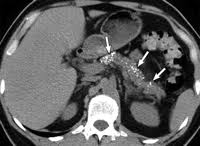

calcific pancreatitis